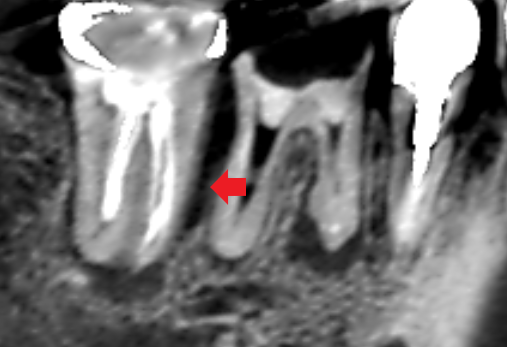

初診時の下顎第一大臼歯と第二大臼歯の矢状断のCT画像です。

赤い矢印の先の下顎第一大臼歯の近心根の根の先に膿の影がみられます。

下顎第二大臼歯の近心根の近心側に歯槽骨の吸収による長い影がみられます。歯根破折が疑えます。